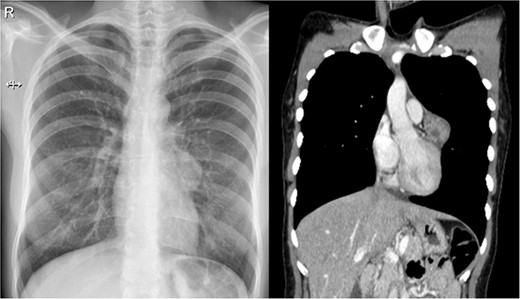

The patient is an otherwise healthy 32-year-old woman. In her youth, for about 3 years, she used to smoke 4–5 cigarettes a day but quit. During a routine medical examination, a standard chest X-ray was needed to obtain an international visa. It unveiled a 30 × 30 mm rounded opacity in the mediastinum; it was surrounded by normal lung parenchyma and was not associated with adenopathies, atelectasis or pleural effusion. Due to this, a contrast-enhanced chest computed tomography (CT) revealed a 38 × 29 × 28 mm heterogeneous solid mass. It was attached to the pericardium and surrounded by the trunk of the pulmonary artery; no other masses or lymph nodes were discovered (Fig. 1).

(a) Chest X-ray: a small rounded mass attached to the heart. (b) Chest CT shows a heterogeneous solid mass with well-defined borders close to the pericardium and near the trunk of the pulmonary artery.